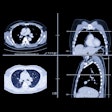

Digital screening mammogram of a 50-year-old woman taking part in the program for the first time. An invasive carcinoma was found, with precancerous microcalcifications nearby. The tumor was at an early stage. All images courtesy of Dr. Walter Heindel and the DRG.Digital screening mammogram of a 50-year-old woman taking part in the program for the first time. An invasive carcinoma was found, with precancerous microcalcifications nearby. The tumor was at an early stage. All images courtesy of Dr. Walter Heindel and the DRG.

Digital screening mammogram of a 50-year-old woman taking part in the program for the first time. The patient had not noticed the relatively superficial tumor, which was at an advanced stage.Digital screening mammogram of a 50-year-old woman taking part in the program for the first time. The patient had not noticed the relatively superficial tumor, which was at an advanced stage.